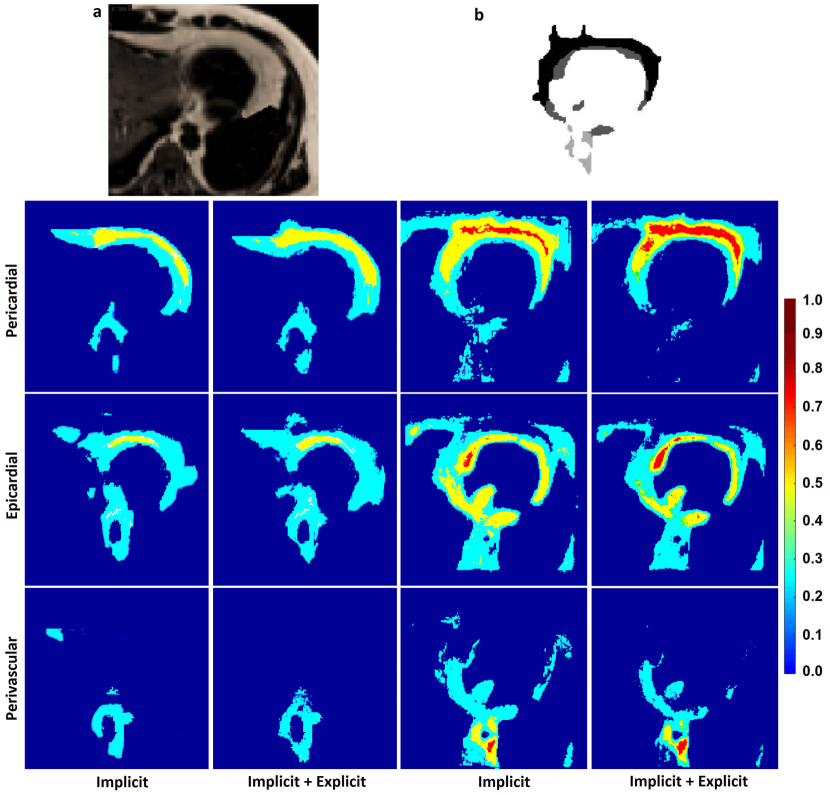

The graphs proposed in section 3 and section 4 tried to implicitly or explicitly detect boundaries between different classes (e.g. objects) in spatial domain (e.g. image). The implicit boundary detection used the Tukey’s function of the features differences of the connected samples and the explicit boundary detection applied a 3D Sobel operator to each intensity channel of the samples. Both of these techniques could enhance the accuracies of a classification in spatial domain. However, their performance was limited when the features of different classes were similar or the boundaries were too weak to be detected. An example of these cases was segmentation of cardiac adipose tissues on fat-water MR images. As shown in Figure 1 and Figure 2 the random forest classifier proposed in [Fallah 2018a, Fallah 2018b, Fallah 2019b, Fallah 2019a] could only detect the overall adipose tissues but could not differentiate different kinds of it. The neighborhood graph proposed in section 3 or section 4 took the priors, the features, and the classification reliabilities of the samples and applied an implicit or explicit boundary detection. This could enhance the accuracy of the segmentation of the cardiac adipose tissues on fat-water MR images but the performance was still unsatisfactory. Figure 7 shows the voxelwise classification posteriors estimated for these adipose tissues by the implicit and/or explicit boundary detection on two axial slices of a fat image. To tackle features similarities and undetectable boundaries between different classes in spatial domain, we further extended the spatial feature-based subgraph by guiding the classification through additional information. These information got encoded into a diffusion-based susceptible-infected-recovered (SIR) model proposed in [Bampis 2017].